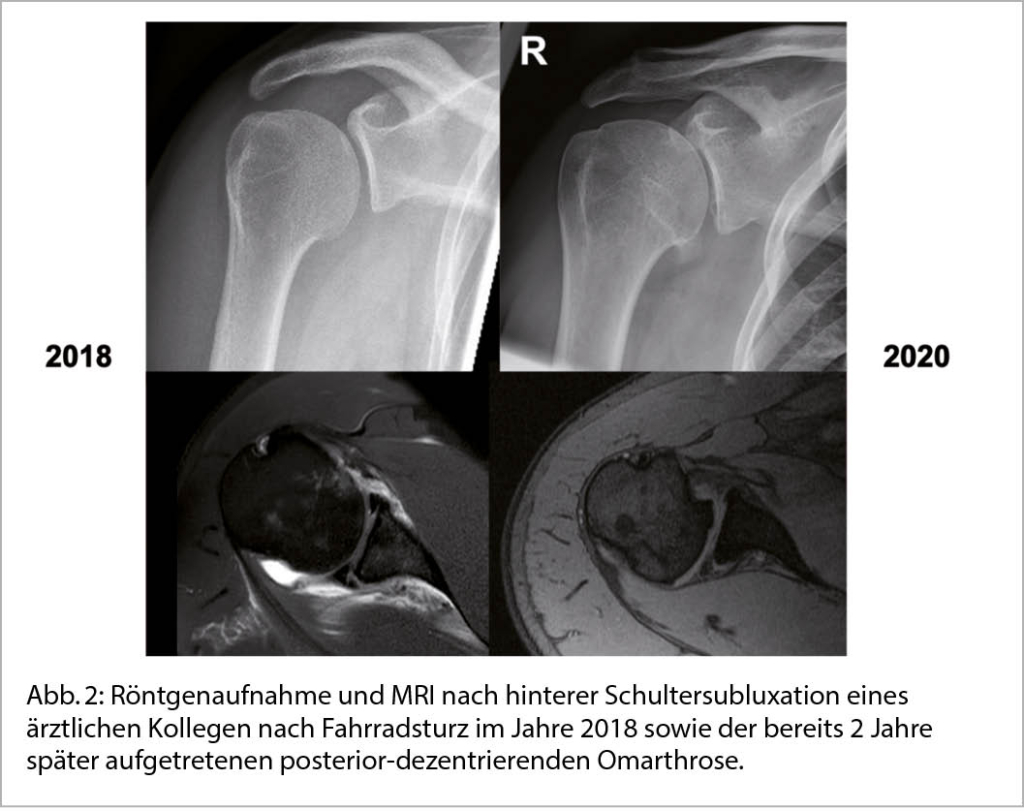

Die sekundäre GHA entstehen auf Basis einer klar definierten Ursache wie z.B. einer Gelenksinstabilität, Fehlstellung nach Trauma, oder einer medikamenteninduzierten Nekrose (Abb. 2).

Tritt eine primäre Arthrose frühzeitig auf, so sollte nach einer versteckten Ursache geforscht werden. Kürzlich konnten wir z.B. in einer Studie zeigen, dass häufig vergleichsweise junge Männer betroffen sind, die Sportarten mit einer hohen Belastung der Schultergelenke ausüben wie z.B. Kraftsport und Kampfsport. Vermeintlich kann eine repetitive Überlastung und ein unausgeglichenes Training zu einer Dysbalance der schulterstabilisierenden Kräftepaare führen und in weiterer Folge eine posterior-exzentrische Arthrose begünstigen (3).